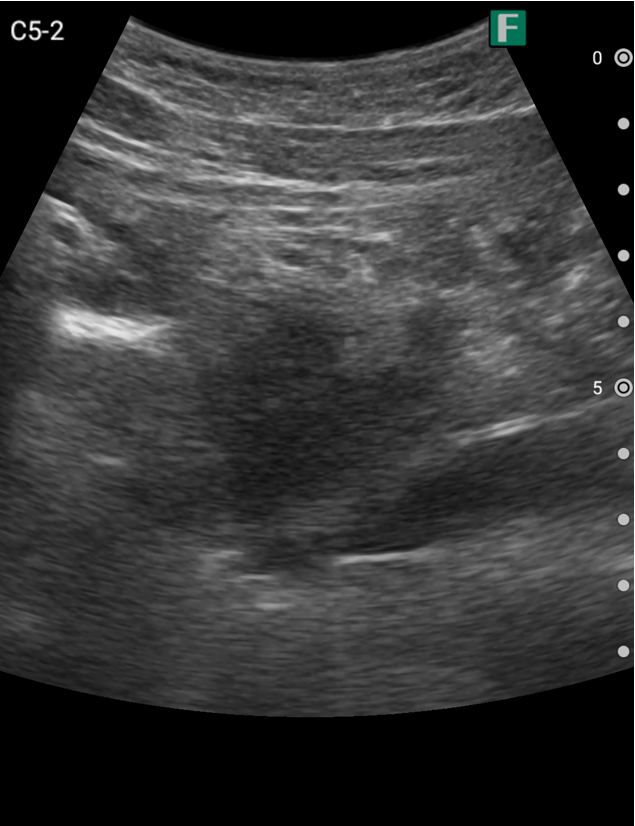

もう一つは入院患者様に対しての具体的な使用事例を紹介します。朝の回診の際にiViz airを使用し、例えば腹水のある患者様を診た際は、「今日は水の量が少なく、そこまでお腹は張ってないですね」、「今日はここに水が溜まっているんですけど、昨日より少ないですよ」など、日々の状態を患者様ご本人に伝えるようにしています。スマホで実際の画像も簡単にお見せできるので、患者様に実際に見ていただくことで少しでも不安を和らげてもらえるように心がけています。

そうして積極的に話をすると、不安そうな表情をする患者様はあまりいらっしゃらない印象を受けています。iViz airがあると患者様と会話をするきっかけにもなるため、コミュニケーションツールとしても実用的だと感じた事例でした。